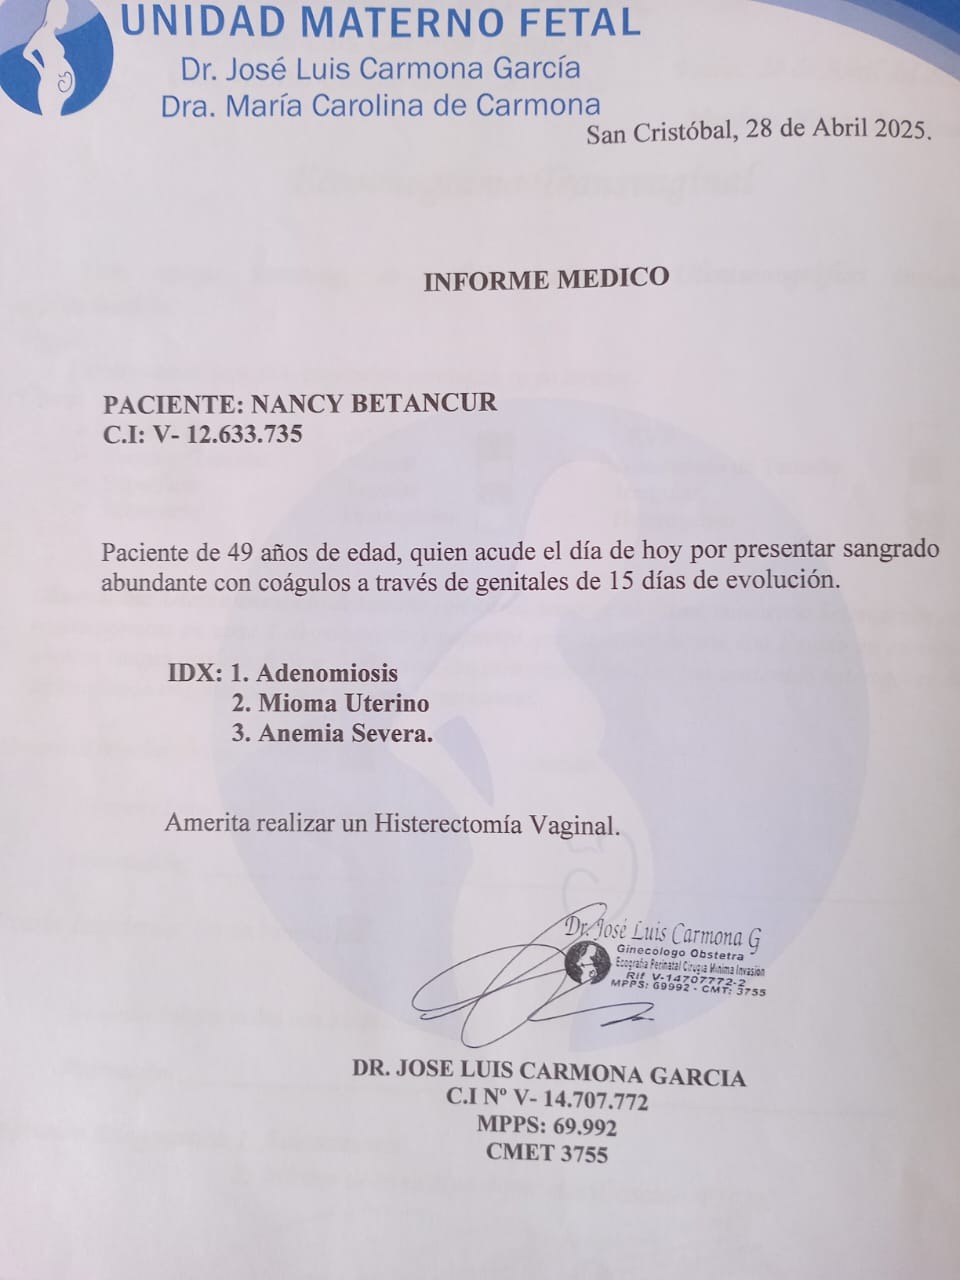

Estoy recaudando fondos para mí madre, en estos momentos pasa por una situación delicada de salud, su diagnóstico requiere de una operación urgente que tiene un costo con el cual no contamos, necesita ser intervenida para mejorar su calidad de vida.

Surgery (Vaginal Hysterectomy)